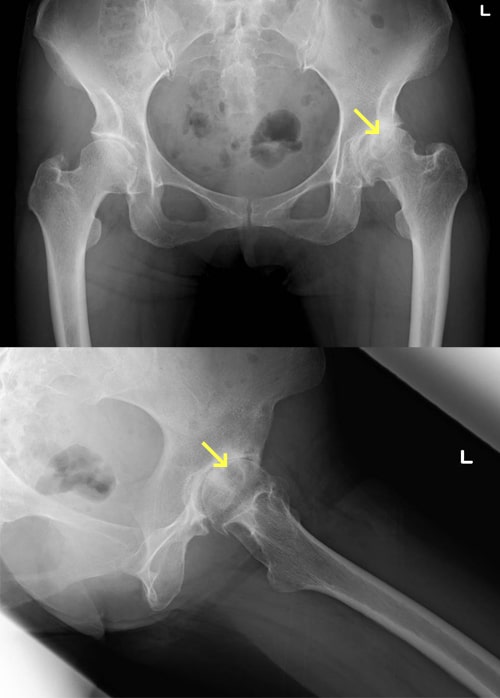

変形性股関節症

主な症状は、股関節の痛みと機能障害です。股関節は鼠径部(脚の付け根)にあるので、最初は立ち上がりや歩き始めに脚の付け根に痛みを感じます。関節症が進行すると、その痛みが強くなり、場合によっては持続痛(常に痛む)や夜間痛(夜寝ていても痛む)に悩まされることになります。一方日常生活では、足の爪切りがやりにくくなったり、靴下が履きにくくなったり、和式トイレ使用や正座が困難になります。また長い時間立ったり歩いたりすることがつらくなりますので、台所仕事などの主婦労働に支障を来たします。階段や車・バスの乗り降りも手すりが必要になります。

患者さんの多くは女性ですが、その場合原因は発育性股関節形成不全の後遺症や股関節の形成不全といった子供の時の病気や発育障害の後遺症が主なもので、股関節症全体の80%といわれています。最近は高齢社会となったため、特に明らかな原因となる病気に罹ったことが無くても年齢とともに股関節症を発症してくることがあります。

変形性股関節症の治療では、初期にはまず消炎鎮痛剤の内服を行います。またもし過体重があるようでしたらダイエットも考えてください。心理的抵抗がなければ杖の使用もお薦めします。一方、痛みがあるとどうしても歩かなくなり筋肉が衰えてしまいますので、できれば水中歩行や水泳(平泳ぎを除く)を行っていただくと理想的です。運動療法はその他の方法もありますが、運動療法はどうしても疼痛を誘発してしまう可能性がありますので、慎重に始めて徐々に強度を高めていくことがポイントです。これらの保存療法でも症状が取れない場合は手術療法を考えます。初期のうちでしたら自分の骨を生かして行う骨切り術の適応ですし、関節の変形がすすんでいる場合は人工股関節手術の適応となります。